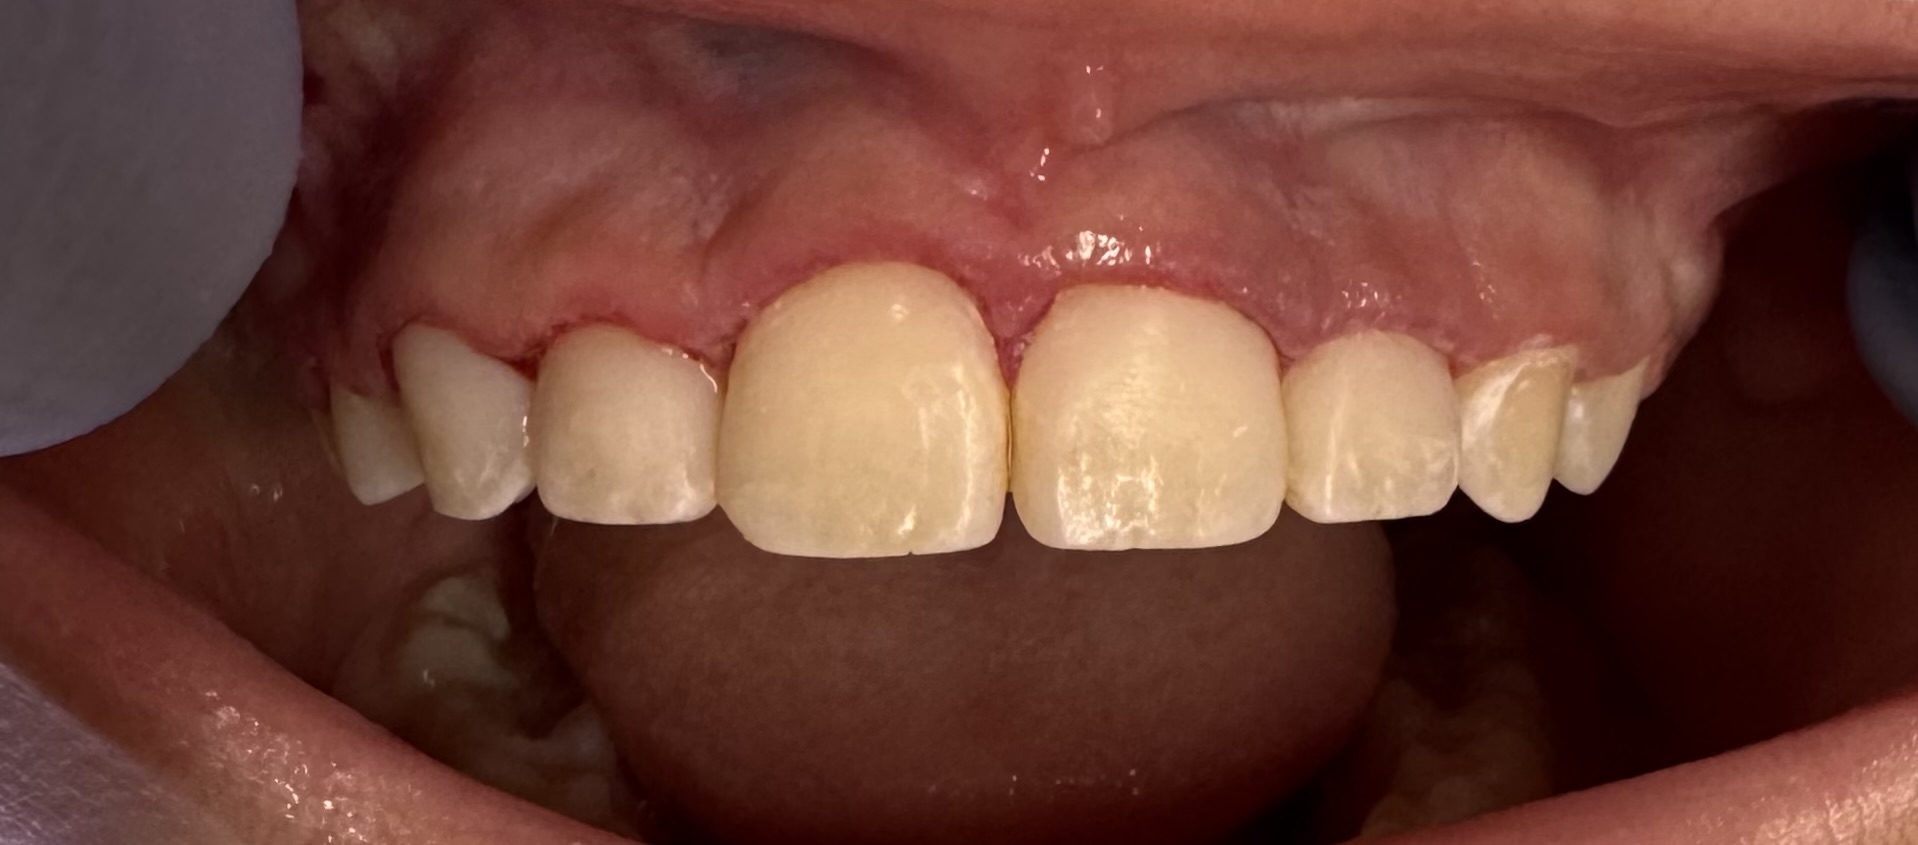

Results – Smile, Speak, and Eat with Renewed Confidence

The transformation achieved for this patient was truly remarkable. Following the treatment plan provided by Dr. Pashmini, the patient was happy with the income. It was a conservative approach since the patient is still a growing teenager. The successful outcome not only resolved their initial dental challenges but also significantly enhanced their quality of life, allowing them to smile, speak, and eat with renewed confidence and comfort.